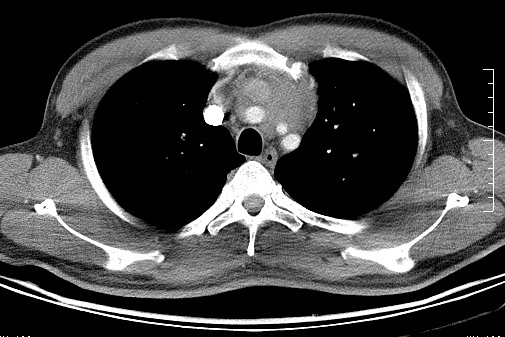

男   40   反复腹痛入院行彩超检查示胸骨右缘4、5肋间不均质回声团

淋巴瘤:前纵隔可见多组肿大的淋巴结,部分融合,有液化坏死

上区却那么有点象占位,胸腺瘤不太象,一点强化也没有,淋巴瘤气管前上腔静后却很干净,下区也点象纵隔积血征,

莲蓬籽征  考虑淋巴瘤